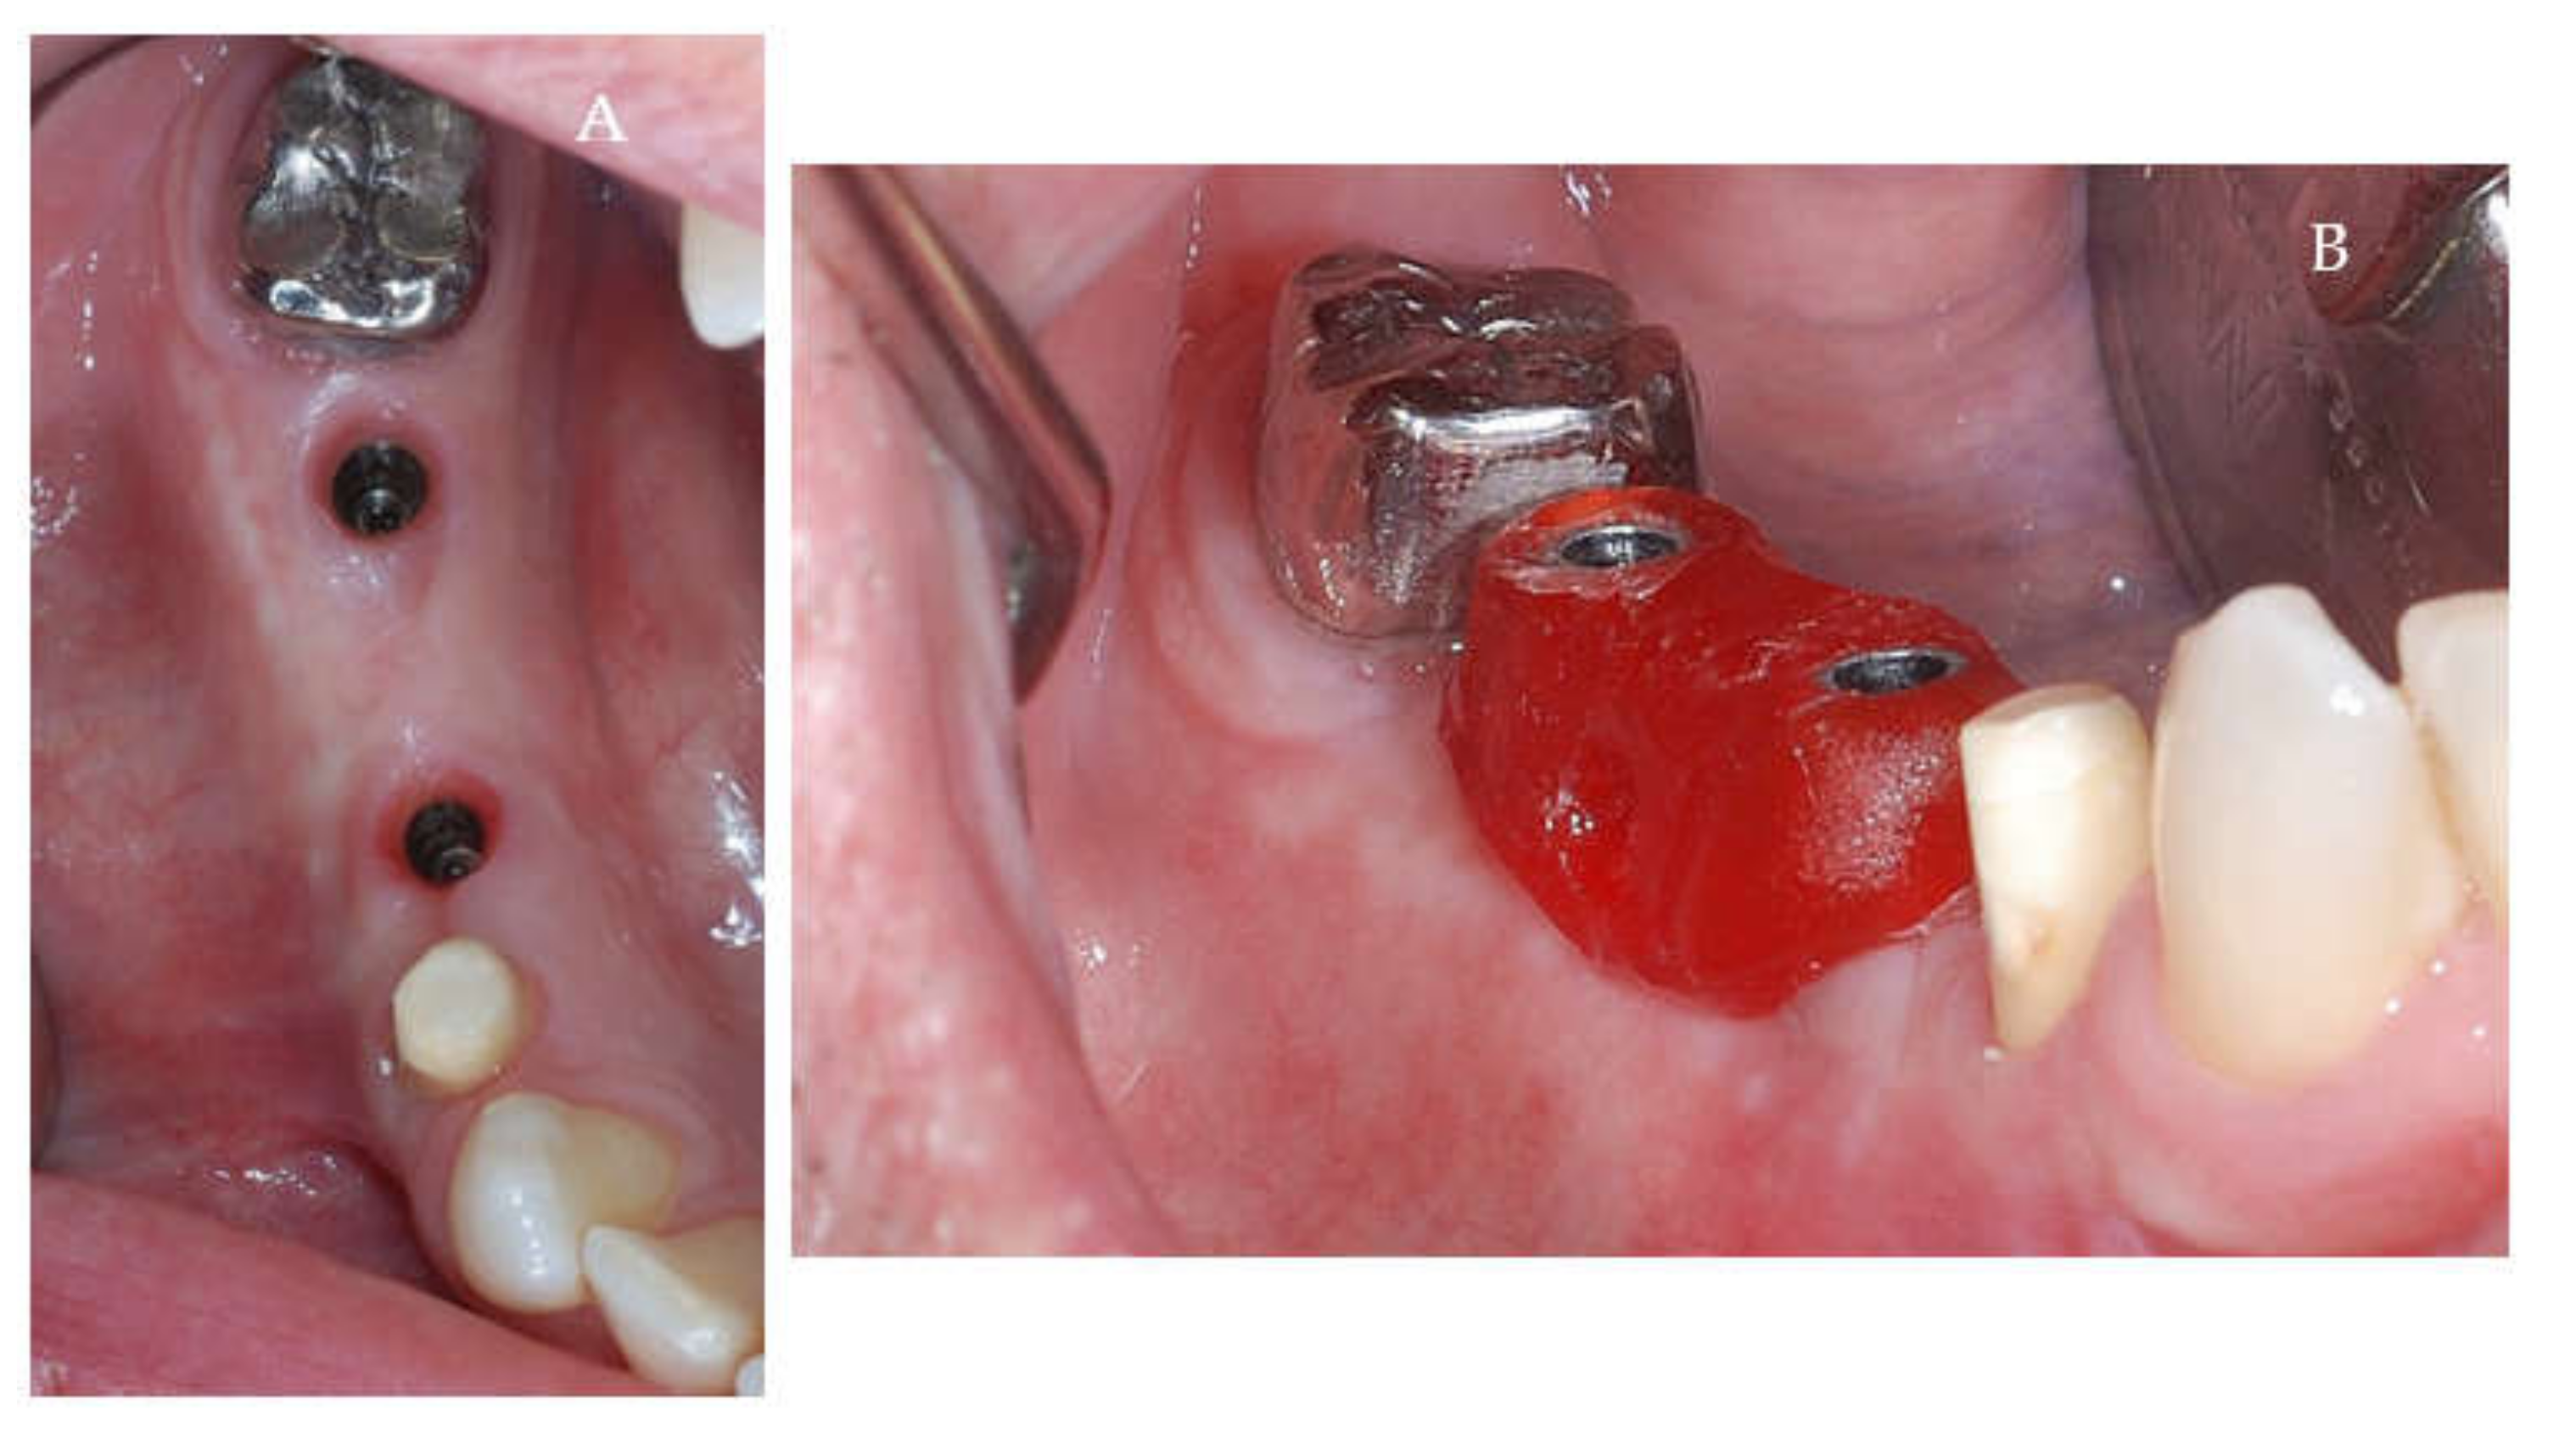

Clinical and CBCT aspects of patient from the test group, describing the stages of S-GBR technique and implant-prosthetic stage, are presented in Figure 1, Figure 2, Figure 3, Figure 4, Figure 5, Figure 6, Figure 7, Figure 8, Figure 9, Figure 10 and Figure 11. CBCT exam allows the evaluation of the horizontal alveolar bone defect and the position of the mandibular alveolar nerf (Figure 1A,B). Figure 1C,D show cross-sectional CBCT aspects of the implant sites. Figure 2 shows the narrowed mandibular alveolar bone with horizontal resorption. Figure 3 shows the exposed buccal surface of the alveolar ridge with severe horizontal resorption, after flap opening. The inserted implants (4.5 mm diameter, 11.5 mm length) and osteosynthesis screws (45° from the occlusal plan) are shown in Figure 4A. The placement of graft (autologous bone and xenograft) and collagen membrane is shown in Figure 4B. Figure 5A shows tension-free sutures, due to periosteal incisions alveolar ridge. Figure 5B shows clinical aspect at 7 months after surgery, with gingival tissue adherent on the reconstructed alveolar ridge. Figure 6 shows OPG aspect at follow-up of 7 months, with osseointegration of the dental implants. Figure 7A shows clinical aspect before osteosynthesis screws removal. Figure 7B shows clinical aspect after osteosynthesis screws removal. Figure 8A shows healthy peri-implant soft tissues. Figure 8B shows repositioning key for perfect position of abutments. Figure 10A,B show clinical aspects of implant-supported prosthetic restoration. Figure 11A,B show CBCT aspects of Osseo integrated dental implants at 24 months follow-up.

Figure 8.

(A,B) Clinical aspects at the second stage surgical session. (A) Aspect before screw removal. (B) Aspect after screw removal.

Figure 9.

(A,B) Post-operative clinical aspects 3 weeks after second stage surgery. (A) Healthy peri-implant soft tissues (B) The repositioning key of abutments.